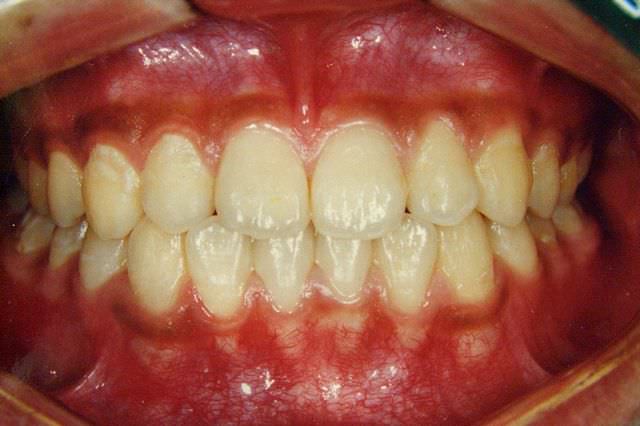

上顎前突 治療前

治療後

上顎前突 治療後

主訴 前歯が出ているのが気になる口が閉じにくい

診断名あるいは主な症状 上顎前突

年齢 11歳4ヶ月

治療に用いた主な装置 ブラケット装置 スタンダードエッジワイズ法

抜歯部位 上下両側第一小臼歯

治療期間 2年11ヶ月

治療費概算 70万+月々の調整料

リスク副作用 歯の根が吸収して短くなる場合があります。

歯茎が痩せて下がる場合があります。

舌で歯を押す唇を噛む等の癖が改善されない場合は、治療期間が長引く場合があります。

定期的に通院できない、キャンセルが多い場合は治療期間が長引きます。